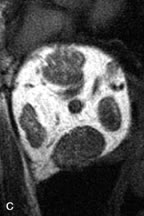

PATIENT PREPARATION Before MRI is performed, patients must be screened and prepared to avoid the potential hazards associated with the strong magnetic field. Patients who have ferrous aneurysm clips or cardiac pacemakers, who depend on life-support equipment, or who retain a possible metallic intraocular foreign body are not candidates for this imaging modality. MRI cannot be performed on obese patients who cannot fit into the bore of the magnet. Patients who are claustrophobic may not tolerate a prolonged period of study within the confines of the magnet, whereas others might do well if given a mild sedative. All worn metallic objects (e.g., necklaces, watches) should be taken off, credit cards set aside, and eye makeup removed before entering the room containing the magnet.5,20,34,35,36 NORMAL ORBITAL ANATOMY T1-weighted images provide the best anatomic details of the orbit because they display superior contrast resolution between normal structures (see Fig. 8). The vitreous has a long T1, resulting in an intermediate signal similar to brain, whereas the crystalline lens and sclera appear dark because of a longer T1 and short T2. The extraocular muscles, like all skeletal muscles, demonstrate a moderately long T1 and short T2 and highly contrast with the intense signal of the surrounding orbital fat (adipose tissue has an extremely short T1). The lacrimal glands appear as mottled areas of reduced intensity of the signal from the orbital fat in the lacrimal fossa. The optic nerves are seen with the same signal intensity as brain white matter and are hypointense relative to the orbital fat because their Tl is longer than the Tl of fat but shorter than the Tl of water. Cortical bone is not well delineated because it contains little free water, yielding minimal signal in MRI, and thus appears dark on all pulse sequences. This feature explains why MR images of the orbital apex and intracanalicular portion of the optic nerves are superior to comparable CT scans. Partial volume averaging of the bones in these regions obscures soft tissue details on CT images, whereas MRI reveals the signals only from the soft tissue structures with no cortical bone input. Bone marrow, on the other hand, is seen as a relatively intense signal because of its high fat content (see Fig. 8).37,38 T2-weighted pulse sequences are not ideal for imaging normal anatomy; however, they are particularly useful in revealing pathologic conditions (see Fig. 9). T2-weighted studies are most easily recognized by a bright vitreous signal. ORBITAL DISEASES Vascular Lesions Cavernous hemangiomas appear as well-circumscribed, smooth, usually intraconal masses that are isointense to muscle on T1-weighted images and hyperintense on T2-weighted images (Fig. 12). Patchy early enhancement is typically followed by diffuse, more homogeneous enhancement.39 The internal architecture of the mass, including septation and internal vasculature, may often be appreciated with high-quality orbital imaging.40 Lymphangiomas consist of ectatic vascular channels within a connective tissue stoma with varying degrees of lymphoid cellularity. On MRI, these tumors are typically poorly circumscribed, multicompartmental, and heterogeneous, often showing cystic dilations with fluid levels (Fig. 13). The signal characteristics within lymphangiomas vary considerably, reflecting cystic and solid components and the varying paramagnetic characteristics of blood at different stages of degradation.40–42 Acute hemorrhage appears hypointense on both T1- and T2-weighted formats. Methemoglobin present in subacute hemorrhage (3 to 14 days) leads to hyperintense signal on both T1- and T2-weighted images.41 A small percentage of lymphangiomas appear radiologically indistinct from orbital cavernous hemangiomas.43 Orbital varices are venous malformations that expand with increased systemic venous pressure, such as with Valsalva maneuvers. Because rapid acquisition of images during a Valsalva maneuver is important in imaging such a lesion, conventional or spiral CT is currently the modality of choice.44 MRI is an excellent modality for demonstrating enlargement of the cavernous sinus and dilation of the superior ophthalmic vein in patients with high-flow carotid-cavernous fistulas (Fig. 14).37MRA may be helpful in the evaluation of the venous outflow pattern. The rapidly flowing blood in these vascular structures carries the excited protons out of the section before they can be imaged, resulting in their dark appearance.5 In low-flow dural arteriovenous malformations, MRA may help define the arterial feeding vessels.45 Neural Lesions MRI is more effective than CT in delineating the intracranial optic nerves, chiasm, and optic tracts and, for this reason, is the preferred imaging modality in the evaluation of optic nerve disorders. The spatial relationships and image contrast of the orbital tissues with intraorbital optic nerve tumors is comparable between the two imaging modalities. The normal nerve is isointense to brain and appears enlarged and kinked owing to infiltration of an optic nerve glioma on T1-weighted images. Gliomas appear hyperintense on T2-weighted images and may be heterogeneous owing to cystic areas within the tumor. Contrast enhancement is variable.46 Intraorbital and intracranial optic nerve sheath meningiomas are usually isointense to cortical gray matter on Tl-weighted images and remain isointense on proton density studies (Fig. 15). Gd-DTPA is useful in delineating the intracranial extension of optic nerve meningiomas.7,47 The hyperostosis of bone and calcification associated with meningiomas are not demonstrated as well on MRI studies as on CT scans.20,37 Gd-DTPA–enhanced MRI also appears promising in the study of the permeability of the blood–brain barrier in selected optic neuropathies.22,48 MRI may reveal an enlarged optic nerve and some degree of contrast enhancement in cases of optic neuritis.49 Muscle Disorders Extraocular muscle enlargement in patients with thyroid-associated orbitopathy is demonstrated equally well with CT and MRI studies. However, the superior tissue contrast on MR images reveals better details of the relationships of the optic nerve to the thickened muscles at the orbital apex (Fig. 16).50 In addition, MRI may be able to differentiate between muscles that are enlarged as a result of edema and active inflammation and those enlarged because of fibrosis by their T2 relaxation times.21 Quantitative MRI was not found to be accurate in predicting the success of low-dose orbital irradiation.51 However, a muscular index relating the diameters of the rectus muscles to the bony orbital dimensions was useful in predicting optic nerve compression.52 MRI is also effective in imaging orbital tumors of mesenchymal origin, such as rhabdomyosarcoma, particularly in the assessment of extension into the anterior and middle cranial fossae (Fig. 17).37 The lack of any pathognomonic radiologic features necessitates rapid orbital biopsy when rhabdomyosarcoma is suspected. Osseous Lesions In general, CT is the imaging modality of choice when details of quantity and quality of bone are needed; however, abnormalities of bones can be detected indirectly by MRI. Cortical bone appears black (signal void) on MR images because of its low proton density and free-water content. The absence or discontinuity of the signal void of the orbital walls may represent bony destruction or fracture. Hyperostosis associated with prostate metastases or meningioma is visualized as areas of black smudging.50,53 Diseases in which the bone is replaced by pathologic tissues with a high free-water content, such as fibrous dysplasia, are well demonstrated on MRI. An intermediate signal intensity on T1-weighted images and hypointense signal on T2-weighted images is representative of fibrous dysplasia. Enhancement on post–Gd-DTPA MR scans is seen and is more evident in areas that are less mineralized.54 Cystic Lesions Dermoid cysts appear as rounded, well-defined lesions typically contiguous with an orbital bony suture. The high-intensity signal on T1-weighted images is attributed to the sebaceous-produced lipid contents (Fig. 18).31,50 Mucoceles may demonstrate a hypointense or hyperintense signal on MR images, depending on the concentration of proteinaceous or inflammatory fluid components. The integrity of the bony walls of the expanded sinus cavities cannot be assessed on MR as well as by CT.37,50,55,56 A high-signal intensity on Tl- and T2-weighted images is characteristic of orbital chronic hematic cysts because of the blood-breakdown products within the cysts.57 Trauma Although soft tissue relationships are usually better demonstrated on MRI, the evaluation of craniofacial bony trauma is preferable with CT. For example, prolapse of orbital fat through a fracture site and hemorrhage of adjacent tissues are demonstrated in an MR image, but the actual fractured bone is not imaged. Three-dimensional MRI of the orbit in subacute trauma has been described,58 although its precise role is not currently established. MRI has been suggested to be superior to CT in detecting intraorbital wooden foreign bodies.59,60 In a series of penetrating orbital injuries with organic foreign bodies, however, MRI was able to identify the foreign body in only four of seven cases.61 With an in vitro model for wood foreign body, McGuckin and colleagues concluded that CT was the imaging modality of choice.62 A careful history and, in selected cases, plain films to rule out a metallic foreign body are crucial before MRI is considered in patients with periocular trauma. MRI is particularly helpful in the detection and characterization of subperiosteal hematomas of the orbit (Fig. 19). They are most commonly seen in the subperiosteal space of the superior orbit as well-defined masses following a traumatic injury. The signal intensity varies depending on the acute, subacute, or chronic nature of the hematoma, based on the stage of blood degradation. Fresh hemorrhages are hypointense on T1-weighted images and hyperintense on T2 images. Hematomas that are 1 to 7 days old are hypointense on both T1- and T2-weighted images. T1-weighted images of hematomas more than a week old are hyperintense due to the oxidation of deoxyhemoglobin to methemoglobin, whereas the T2 images remain hypointense.63 Metastatic Tumors Breast carcinoma metastatic to the orbit has been demonstrated to be hypointense to the surrounding orbital fat on T1-weighted studies and hyperintense on T2-weighted images and has an affinity to the extraocular muscles (Fig. 20).50,64 The MRI characteristics of prostate carcinoma metastatic to the orbit have been described as involving the greater and lesser wing of the sphenoid, orbital roof, and optic canal. Diffuse bone hypertrophy with isointense or slightly hyperintense tissue on T1-weighted images represents the osteoblastic carcinomatous bone infiltration. Contrast enhancement is variable on T1-weighted and fat-suppressed images.65 Most other metastatic tumors also have a lower intensity signal on T1-weighted images and appear to displace or infiltrate normal orbital structures; however, their signal characteristics are variable on T2-weighted MR images.66 Many metastatic tumors demonstrate bright contrast enhancement with Gd-DTPA. Infectious Disorders MRI findings of preseptal and orbital cellulitis typically include increased signal intensities on T2-weighted images of the eyelids and orbital fat, respectively, due to the increased water content of the tissues. Since most cases of bacterial orbital cellulitis are associated with paranasal sinusitis, hyperintense signals of the affected sinuses may also be found on T2-weighted images as well as enhancement of polyps and granulation tissue on postgadolinium T1-weighted MR images. Subperiosteal abscess formation may occur due to contiguous spread of infection from the paranasal sinuses and appear on MRI as an area of intermediate signal on T1-weighted and proton-weighted MR images. The abscess may appear slightly hyperintense compared with muscle on T2-weighted scans with the necrotic contents having the greatest intensity.67 MRI and MRV are more sensitive than CT in revealing cavernous sinus thrombosis. Engorgement of the cavernous sinus, extraocular muscles, and ophthalmic veins is seen with hyperintensity of the thrombosed sinuses evident on all pulse sequences. The enlarged, thrombosed superior ophthalmic vein appears less hypointense than the normal contralateral ophthalmic vein, and hyperintensity within the lumen of the vessel may be seen on T1- and T2-weighted MR images.68 Inflammatory and Lymphoproliferative Lesions Inflammatory conditions of the orbit, both idiopathic (inflammatory pseudotumor) and those of known causes, have been found to be hypointense to fat and isointense to muscle on Tl-weighted studies and isointense or slightly hyperintense to fat on T2-weighted images (Fig. 21).50,64,69 The more fibrous or sclerosing varieties have less signal intensity on T2-weighted images. Marked enhancement is seen in pseudotumor infiltrates after gadolinium administration.70 The same signal characteristics are demonstrated in patients with Tolosa-Hunt syndrome, with mass lesions seen in the cavernous sinuses and orbital apices.71 Lymphomas have MRI characteristics similar to those of inflammatory lesions in that they are hypointense to fat and isointense to muscle on T1-weighted images (Fig. 22). They may appear hyperintense to fat on T2-weighted images, perhaps owing to less fibrosis than that seen in orbital inflammatory pseudotumor, although this is not a consistent finding.31,50,66 Lymphoid tumors typically enhance moderately after contrast injection. Unfortunately, studies have shown that tumor density and homogeneity are similar between inflammatory and malignant orbital infiltrates, and MRI cannot differentiate these lesions.72,73 Lacrimal Gland Tumors Lacrimal gland lesions present special problems in diagnosis and management. Pleomorphic adenoma (benign mixed tumor) should not be biopsied, but rather excised in toto. On the other hand, for lymphoma and inflammatory infiltrates, incisional biopsy is more appropriate than complete excision of the lacrimal gland. Thus, preoperative clinical and radiologic evaluation are especially crucial in planning appropriate surgical management. Pleomorphic adenomas demonstrate long T1 and T2 signal characteristics. They may show heterogeneity on T2-weighted images74 and moderate to marked enhancement with contrast.75 Signal characteristics of adenoid cystic carcinoma include hypointensity to fat on T1-weighted images, hyperintensity to fat with increased T2 weighting, and isointensity to fat on proton density-weighted studies (Fig. 23).31,75 Secondary bony alterations of the lacrimal fossa associated with lacrimal gland tumors, such as remodeling (benign mixed tumor) or destruction (adenoid cystic carcinoma), are seen indirectly on MR images; however, bone windows on CT scans provide better delineation of these changes. In contrast to the round or globular appearance of benign or malignant epithelial tumors of the lacrimal gland, lymphoproliferative tumors usually appear to be molding or draping onto the globe and the surrounding bony orbit. LACRIMAL DRAINAGE SYSTEM DISORDERS MRI with surface coils provides excellent spatial resolution and tissue-specific signal intensities of the lacrimal drainage system. These parameters have been found useful to more accurately demonstrate the extent of lesions in the lacrimal sac and differentiate long-standing mucoceles from solid tumors than CT.76 Physiologic studies in patients with tearing disorders now include MR dacryocystography, in which Gd-DTPA is either placed topically in the conjunctival fornix or injected by cannulation into the lacrimal sac. They provide a detailed morphologic and functional analysis of the lacrimal excretory system; however, they are no more sensitive than digital-subtraction dacryocystography or CT dacryocystography.77–79 INTRAOCULAR TUMORS On MRI, uveal melanomas have a typical appearance that helps to differentiate them from other primary and secondary intraocular tumors as well as choroidal detachments. Pigmented melanomas are hyperintense on Tl-weighted images, hypointense on T2-weighted studies, and hyperintense on proton density–weighted examinations (Fig. 24).30,31,50,80–82 These signal characteristics have been attributed to the paramagnetic properties of melanin because of stable free radicals that shorten the T1 and T2 relaxation times. Moderate enhancement is seen on postgadolinium T2-weighted images. Gadolinium-enhanced T1-weighted images are particularly sensitive in detecting choroidal melanomas.83 MRI may be less sensitive in detecting extrascleral extension of tumor than echography performed by an experienced ultrasonographer.84 Tumors metastatic to the choroid are hyperintense on T1- and T2-weighted images.24 The signal characteristics, however, may be similar to those seen with choroidal melanoma. Choroidal hemangiomas, on the other hand, have an intermediate signal on T1-weighted sequences and become hyperintense on T2-weighted images50 as well as proton density–weighted images.81 Retinoblastomas display moderate signal intensity on T1-weighted studies and a low signal on T2-weighted images.31,80,85 Calcification can be easily detected by CT and ocular ultrasonography but is not imaged by MRI.25,50 The presence of optic nerve involvement is best evaluated by MRI. ACQUIRED ANOPHTHALMIA When an eye is removed owing to tumor or trauma, an implant is typically placed in the intraconal space. MRI may be useful in defining the size, shape, and position of such orbital implants.86 Porous hydroxyapatite or polyethylene implants are preferred by many surgeons performing enucleation or evisceration. A porous implant offers the possibility of supporting a motility coupling peg to increase the movement of the overlying prosthesis. MRI with contrast is used by some surgeons to evaluate the degree of fibrovascular ingrowth in hydroxyapatite87 and porous polyethylene88 implants prior to motility peg placement. |